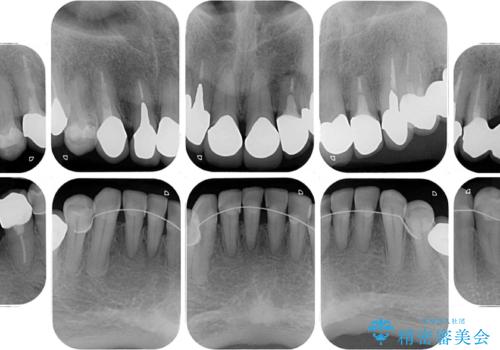

並行して左下にはインプラントを埋入し、上顎臼歯部の気になる部分も根管治療などを進めて行き、矯正治療を終えると同時に補綴治療を行うこととしました。

奥歯1歯分を動かすには時間がかかるため、矯正治療には思いの外時間がかかりました。

痛みのある奥歯は必要に応じて根管治療を行い、左下インプラントは角化歯肉の移植により清掃性を向上させ、気になっていた部分をしっかりと改善させることができました。